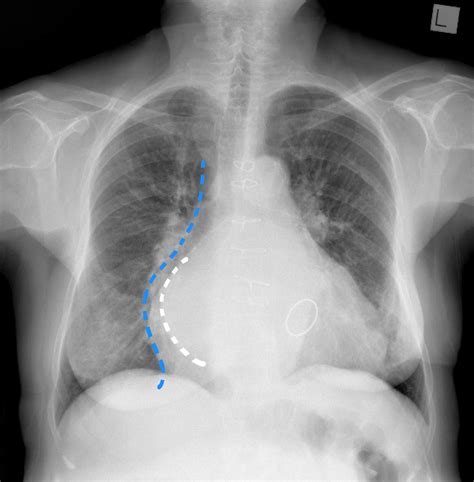

Web the double density sign, also sometimes clumsily referred to as the hotter spot within hot area sign, is a bone scan sign of an osteoid osteoma. Being an anatomical sign it can be seen on all modalities that can visualize the region, including: Web double density sign of berry aneurysms refers to the angiographic appearance of a small intracranial aneurysm projecting in front or behind a vessel of similar caliber. Mri, ct, ultrasound and endoscopic retrograde cholangiopancreatography ( ercp ). It is seen with large amounts of pneumoperitoneum (>1000 ml). Diagnosis is made radiographically with foot radiographs with ct scan often being required for surgical planning. As such, the border of the aneurysm cannot easily be seen, but the extra contrast within it can be seen as a rounded area of increased density. Gas within the bowel's lumen and gas within the peritoneal cavity. If large enough, the left atrium. Web the double duct sign refers to the presence of simultaneous dilatation of the common bile and pancreatic ducts. Web the double density sign, also sometimes clumsily referred to as the hotter spot within hot area sign, is a bone scan sign of an osteoid osteoma.